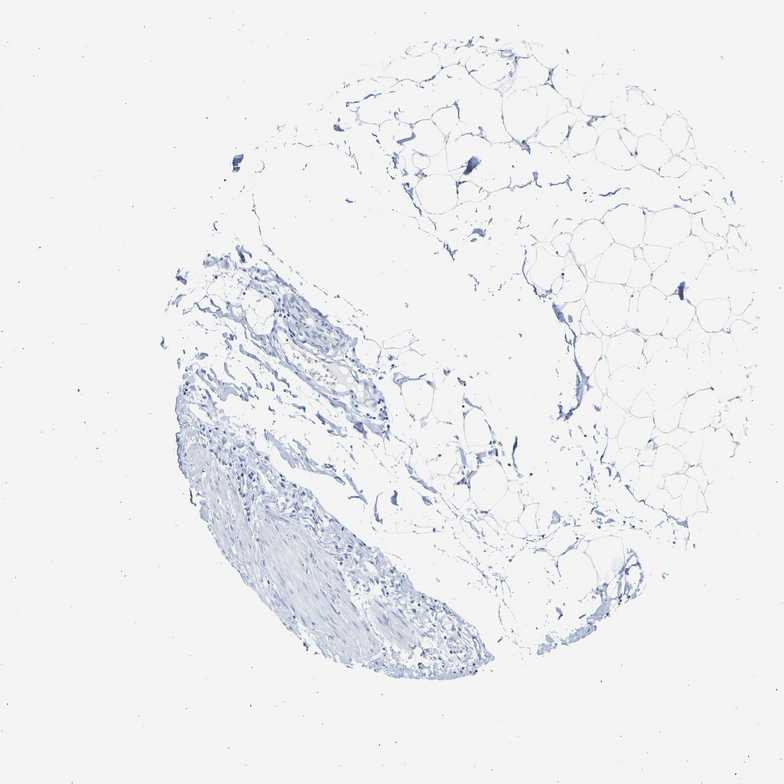

SOFT TISSUE 1 - Antibody stainingi

Antibody staining in the annotated cell types in the current human tissue is reported as not detected, low, medium, or high, based on conventional immunohistochemistry profiling in selected tissues. This score is based on the combination of the staining intensity and fraction of stained cells.

Each image is clickable and will lead to virtual microscopy that enables deeper exploration of all samples and also displays staining intensity scores, fraction scores and subcellular localization as well as patient and tissue information for each sample.

Antibody HPA026813Antibody CAB020824

Chondrocytes Not detected-

Fibroblasts Not detectedNot detected

Peripheral nerve Not detectedNot detected